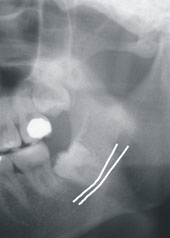

※下顎深部智齒靠近下顎神經(兩白線中間)及上顎阻生智齒

拔完智齒常見的後遺症不外乎是腫及痛。痛是主觀感受,短則一兩天,長則一、二週都有可能。幾乎所有水平智齒拔完回去都會腫,腫脹其實是人體自然發炎反應的一部分,通常都會在前三天越來越腫,一周週後慢慢消退、產生瘀青。另外大家常聽到的就是診所醫師跟你說你的牙根很靠近神經,請你到大醫院拔。到底牙根靠近神經會怎麼樣?其實牙醫師在判斷這個情況是靠全口X光片來看,X光片拍攝出來是一個平面的圖片,但是在嘴巴裡面牙齒、骨頭以及神經都是一個立體的構造。有時候只是前後位置重疊,不一定是牙根真的靠在神經上。大家需要了解的其實是傷到神經的後遺症,畢竟牙齒有問題如果不處理,產生蜂窩性組織炎等等的情況可能會更嚴重。拔智齒時若是真的傷到神經,病患在拔完智齒麻藥退了之後,會覺得嘴唇、臉頰或是舌頭麻麻的,感覺怪怪的,但是不會有臉歪嘴斜、漏口水的情況。外觀上看其實都是正常的,只是病患感覺會比較麻木,恢復的時間因人而已,根據神經修復的速率,可能一週到數年都有可能,但是發生的機率並不是很高。